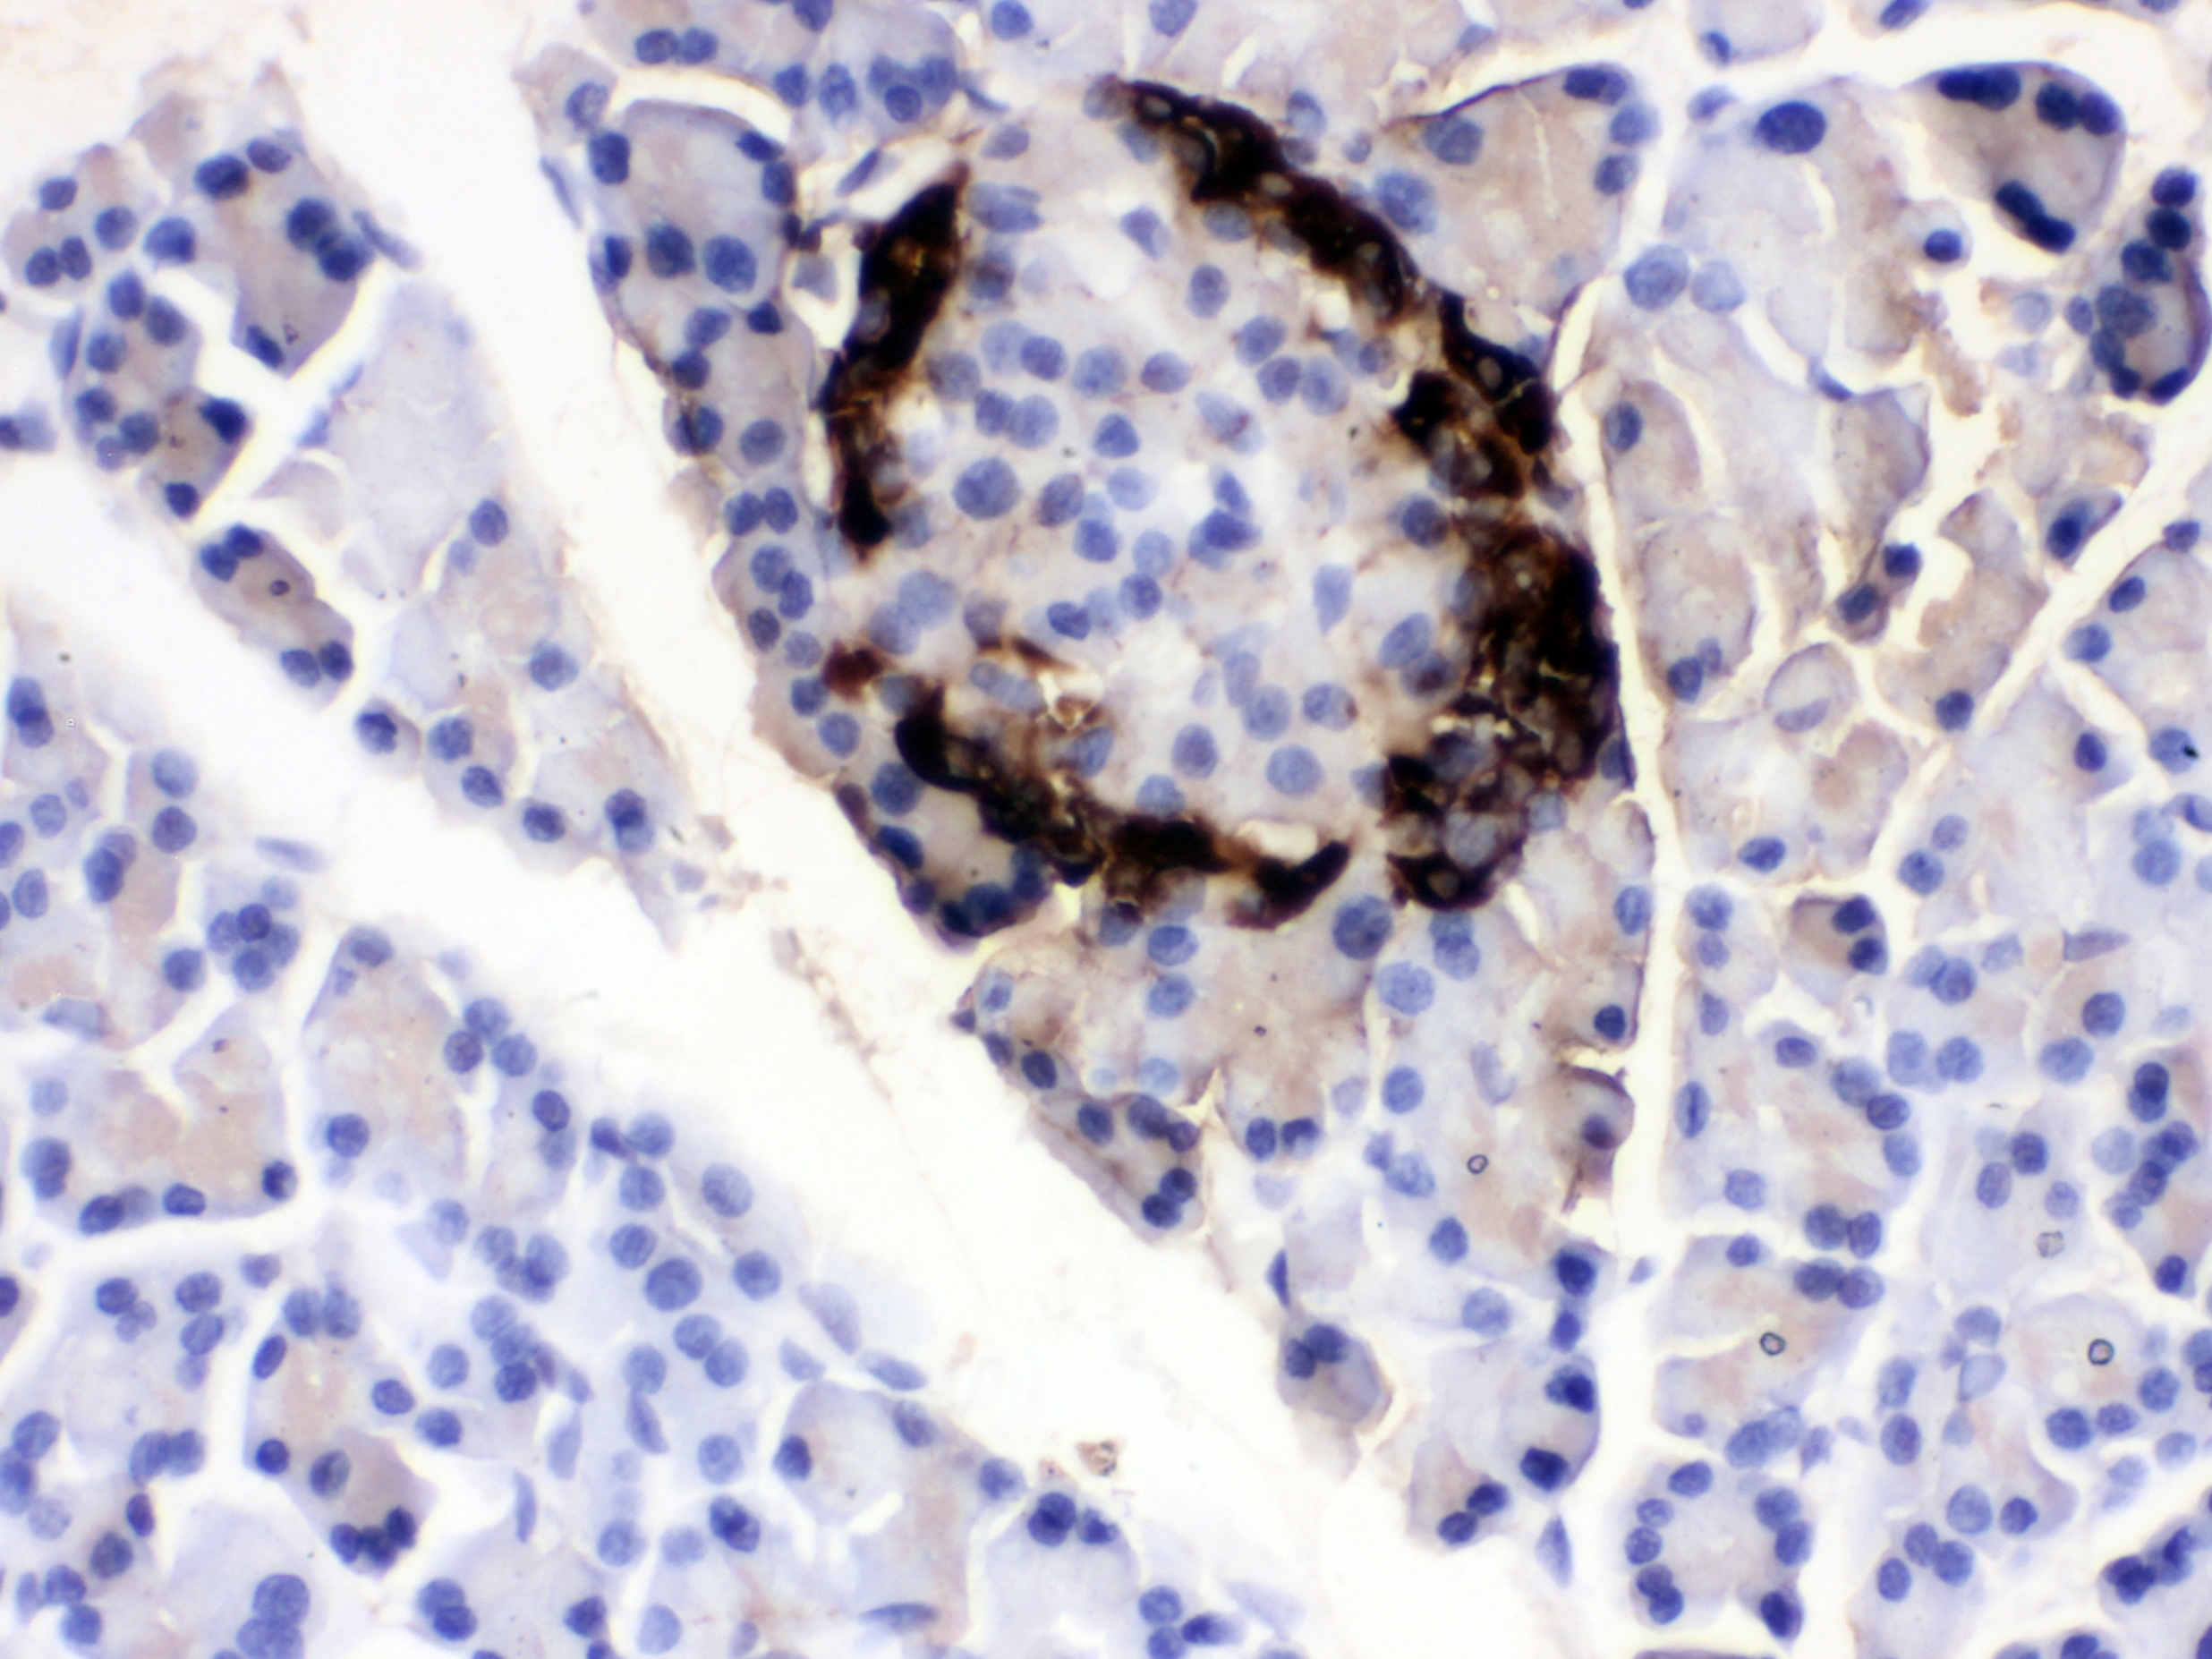

IHC analysis of VIP using anti-VIP antibody (PB1017).

VIP was detected in a paraffin-embedded section of human pancreatic cancer tissue. Biotinylated goat anti-rabbit IgG was used as secondary antibody. The tissue section was incubated with rabbit anti-VIP Antibody (PB1017) at a dilution of 1:200 and developed using Strepavidin-Biotin-Complex (SABC) (Catalog # SA1022) with DAB (Catalog # AR1027) as the chromogen.